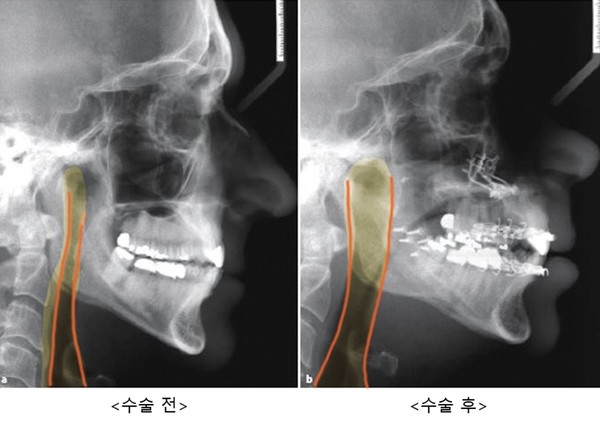

반면 ‘양악 전진술’은 수면무호흡증 치료 성공률이 75~100%에 이를 정도로 지금까지 알려진 외과적 치료 중 가장 높은 성공률을 보인다. 위턱과 아래턱을 10mm 내외 전방으로 이동시키는 수술로서, 상기도 전체를 넓혀주어 치료한다. 쉽게 설명하자면 주걱턱의 치료와 반대로 위턱과 아래턱을 앞으로 이동시켜 기도를 확보하는 수술이다.

양악 전진술 시 이론적으로는 양악이 전진하는 양이 많으면 많을수록 좋은 효과를 기대할 수 있다.

서양인(주로 백인)의 경우 8~12mm정도를 전진하지만, 동양인은 코가 낮고 입술이 돌출된 경우가 많아 동일한 양의 전진은 얼굴의 심미성을 해칠 수 있으므로 수면무호흡증의 정도와 외모를 분석하여 양악 전진술의 양을 결정하는 것이 중요하다.